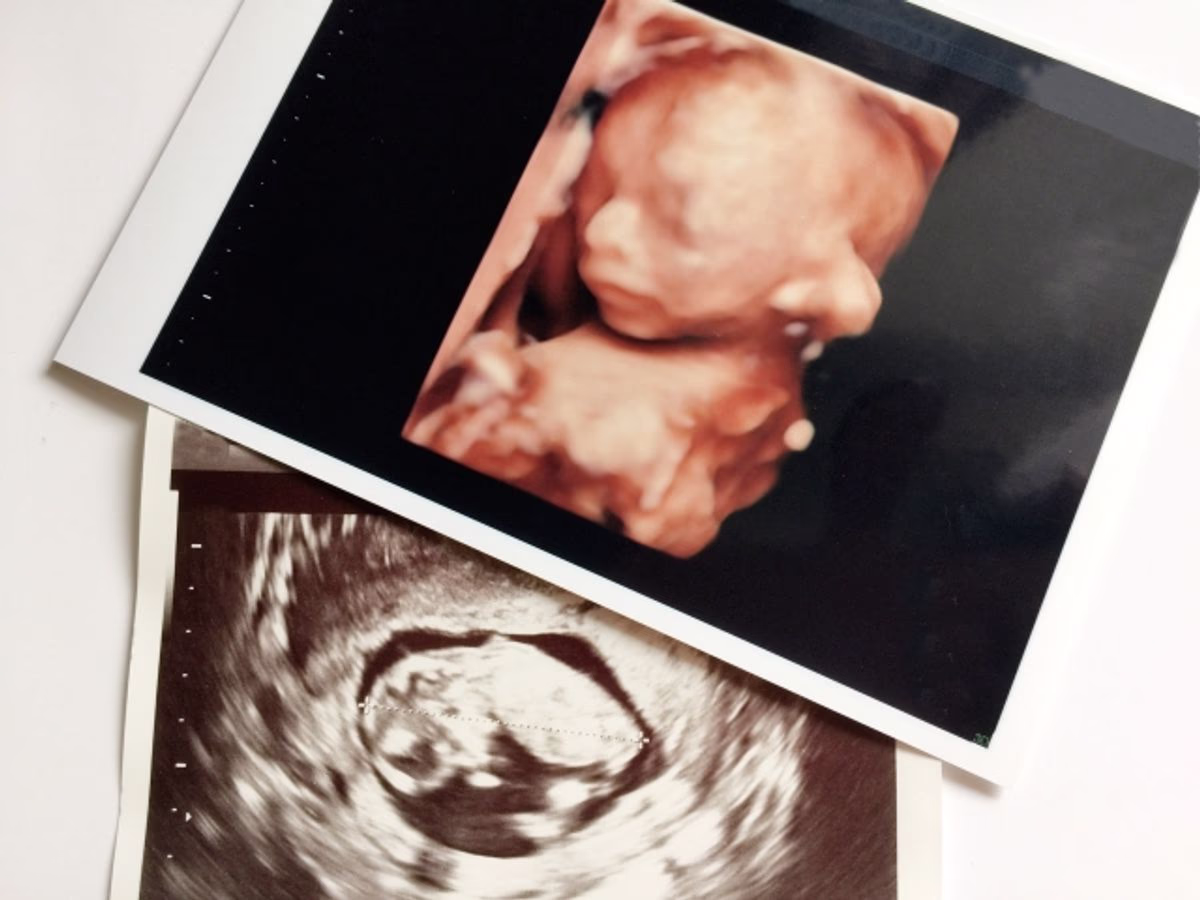

超音波検査(エコー)で確認できる

超音波検査(エコー)では、赤ちゃんの外性器の形で性別を判定します。

■男の子の場合

両足の間に陰茎と陰嚢が確認できます。陰茎は、体に対して垂直な突起物として映ることが多いです。

■女の子の場合

女の子の外性器はエコーで映りにくいため、はじめは「男の子ではないから女の子かな?」と推測されます。

17~18週頃になると、木の葉のような形が見えるようになり、女の子と判定できます。

妊婦検診で、医師と一緒に確認してみてくださいね。